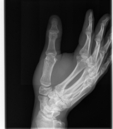

Broken Hand

This was just a hairline fracture that I managed to get from a soccer game. I thought it was pretty cool that I was given all of the digital copies.

Broken Hand (264474)